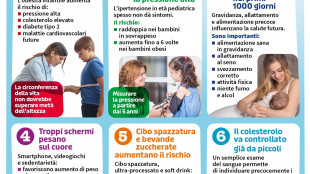

Obesità, diabete e ipertensione, i rischi per il cuore iniziano da piccoli

Linee guida dai pediatri: "Monitorare pressione e colesterolo già nei primi anni di vita"